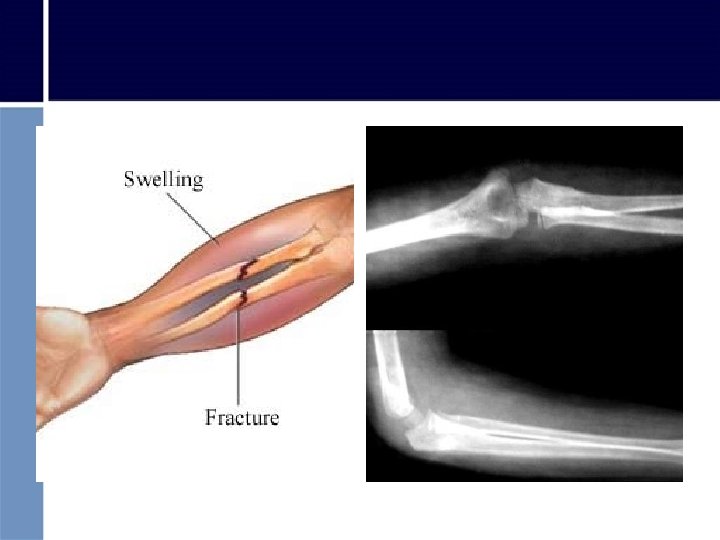

FRACTURA DE CODO

FRACTURA DE CODO • Inmovilizar de la misma manera en que se encontró • En extensión: – Colocar férula desde axila hasta antebrazo y atar con venda – Asegurar brazo contra el cuerpo • En flexión: – Sujetar brazo sobre el pecho con cabestrillo – Idem fractura antebrazo